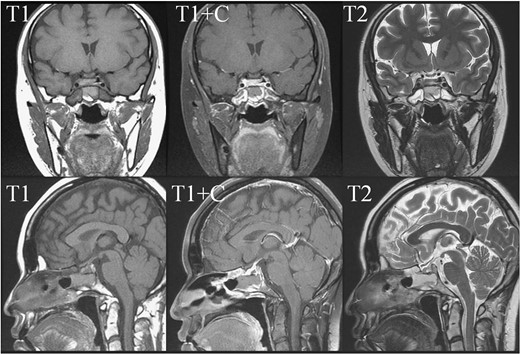

In May 2018, a 28-year-old woman with medical history of sick sinus syndrome and mitral valve prolapse, who just gave birth to a child in April 2018 coming to our Emergency Department with the chief complaint of severe headache and blurred vision for one week. At the Emergency Department, her visual acuity was 0.1 on her right eye and 0.9 on her left eye. Brain CT (computed tomography) scan was checked showing increased soft tissue density over sellar and suprasellar regions, more on the right side. Sellar MRI (magnetic resonance imaging) (Fig. 1) was further arranged which showed a mass with rim enhancement about 2.2 cm ×1.4 cm ×1.2 cm in size located at sella with suprasellar extension with several suspected hemorrhagic foci inside. Under the impression of pituitary apoplexy, she was admitted for further evaluation and management. On admission, her neurological examination showed essentially negative findings except declined right visual acuity; her hormone study showed low level of cortisol (cortisol<1.00 μg/dL) and others were within normal limits. Before surgery, ophthalmologist was consulted again to repeat her ophthalmological examination. The visual acuity of her right eye and left eye improved to 0.8 and 1.0 respectively after the use of steroid. The visual field test showed peripheral defect over the upper visual field of both eyes. Under general anesthesia, she underwent endoscopic endonasal transsphenoidal approach with the removal of tumor and skull base reconstruction. Grossly, the tumor was yellow and soft in consistency and at the end of the procedure, the pituitary gland was well exposed and visible (Fig. 2). After surgery, her vision was subjectively improved; her cortisol level returned to normal (cortisol=16.6ug/dL) and other hormonal data were within normal limits. Histology examination of the tumor (Fig. 3) showed that it composed of spindle to epithelioid cells forming poorly defined lobules and interlacing fascicles, both featuring eosinophilic and oncocytic cytoplasm, with mild nuclear atypia. Immunohistochemically, the neoplastic cells showed TTF-1(+), GFAP(-), EMA(+) Annexin A1(+), and PAS/DPAS(-). Based on the result of histopathology findings and immunohistochemical stains, spindle cell oncocytoma was diagnosed. Before discharge home, her early post-operative sellar MRI (Fig. 4) showed neither residual nor recurrent lesion; she was discharged in a good condition.

Pre-operative sellar MRI. The coronal view (upper row) and sagittal view (lower row) demonstrated a mass about 2.2 cm ×1.4 cm ×1.2 cm in size, located at sella with suprasellar extension. The mass lesion showed low intensity in T1 weighted image, high intensity in T2 weighted image, and rim enhancement after gadolinium injection. Inside the mass, several foci showing high intensity in T1 weighted image, low intensity in T2 weighted image and no enhancement after gadolinium injection were present.

Early post-operative sellar MRI. The coronal view (upper row) and sagittal view (lower row) showing the status post removal of the tumor over the sellar and suprasellar regions with poor-enhancing area at the posterior sellar region which favored postoperative change.